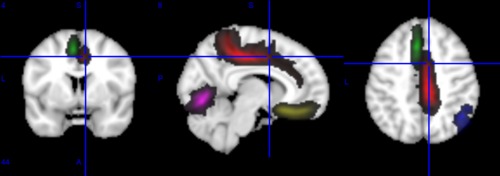

Probability maps

Probability maps corresponding to a few anatomical landmarks (cortical folds) overlaid on a T1 template